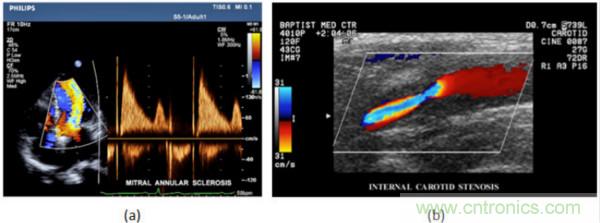

在CW和PW多普勒模式中,流信息是從一個(gè)聚焦聲束中獲得的,類似于A模式成像。在20世紀(jì)80年代,研究人員基于彩色多普勒技術(shù)完成了血流分布的二維信息可視化。彩色多普勒處理也是基于B模式/PW模式信號(hào)路徑。從感興趣區(qū)域收集多幀RF數(shù)據(jù)。由于感興趣區(qū)域中的血液流動(dòng)導(dǎo)致圖像幀之間存在數(shù)據(jù)差異。相域中的自相關(guān)和時(shí)域中的互相關(guān)兩種算法可從RF數(shù)據(jù)中提取數(shù)據(jù)方差(即血流速度和方向信息):。根據(jù)預(yù)定義的顏色漸變條相應(yīng)地映射包括速度和方向的血流信息。通常,藍(lán)色和紅色代碼分別識(shí)別朝向和遠(yuǎn)離換能器移動(dòng)的血流。當(dāng)流速增加時(shí)使用更亮的顏色,反之亦然。顏色映射的2D分布始終疊加在B模式圖像上,以實(shí)時(shí)同時(shí)顯示個(gè)體解剖結(jié)構(gòu)和血流。它對(duì)于診斷心血管疾病,如血管閉塞和心臟瓣膜反流,極其有用。典型的彩色多普勒?qǐng)D像如下圖所示,(b)顯示頸動(dòng)脈狹窄引起的血流流速變化。

圖7.彩色多普勒成像:(a)以彩色多普勒和CW模式獲得的圖像(由Philips提供); (b)顯示頸動(dòng)脈狹窄的彩色多普勒(由GE提供)